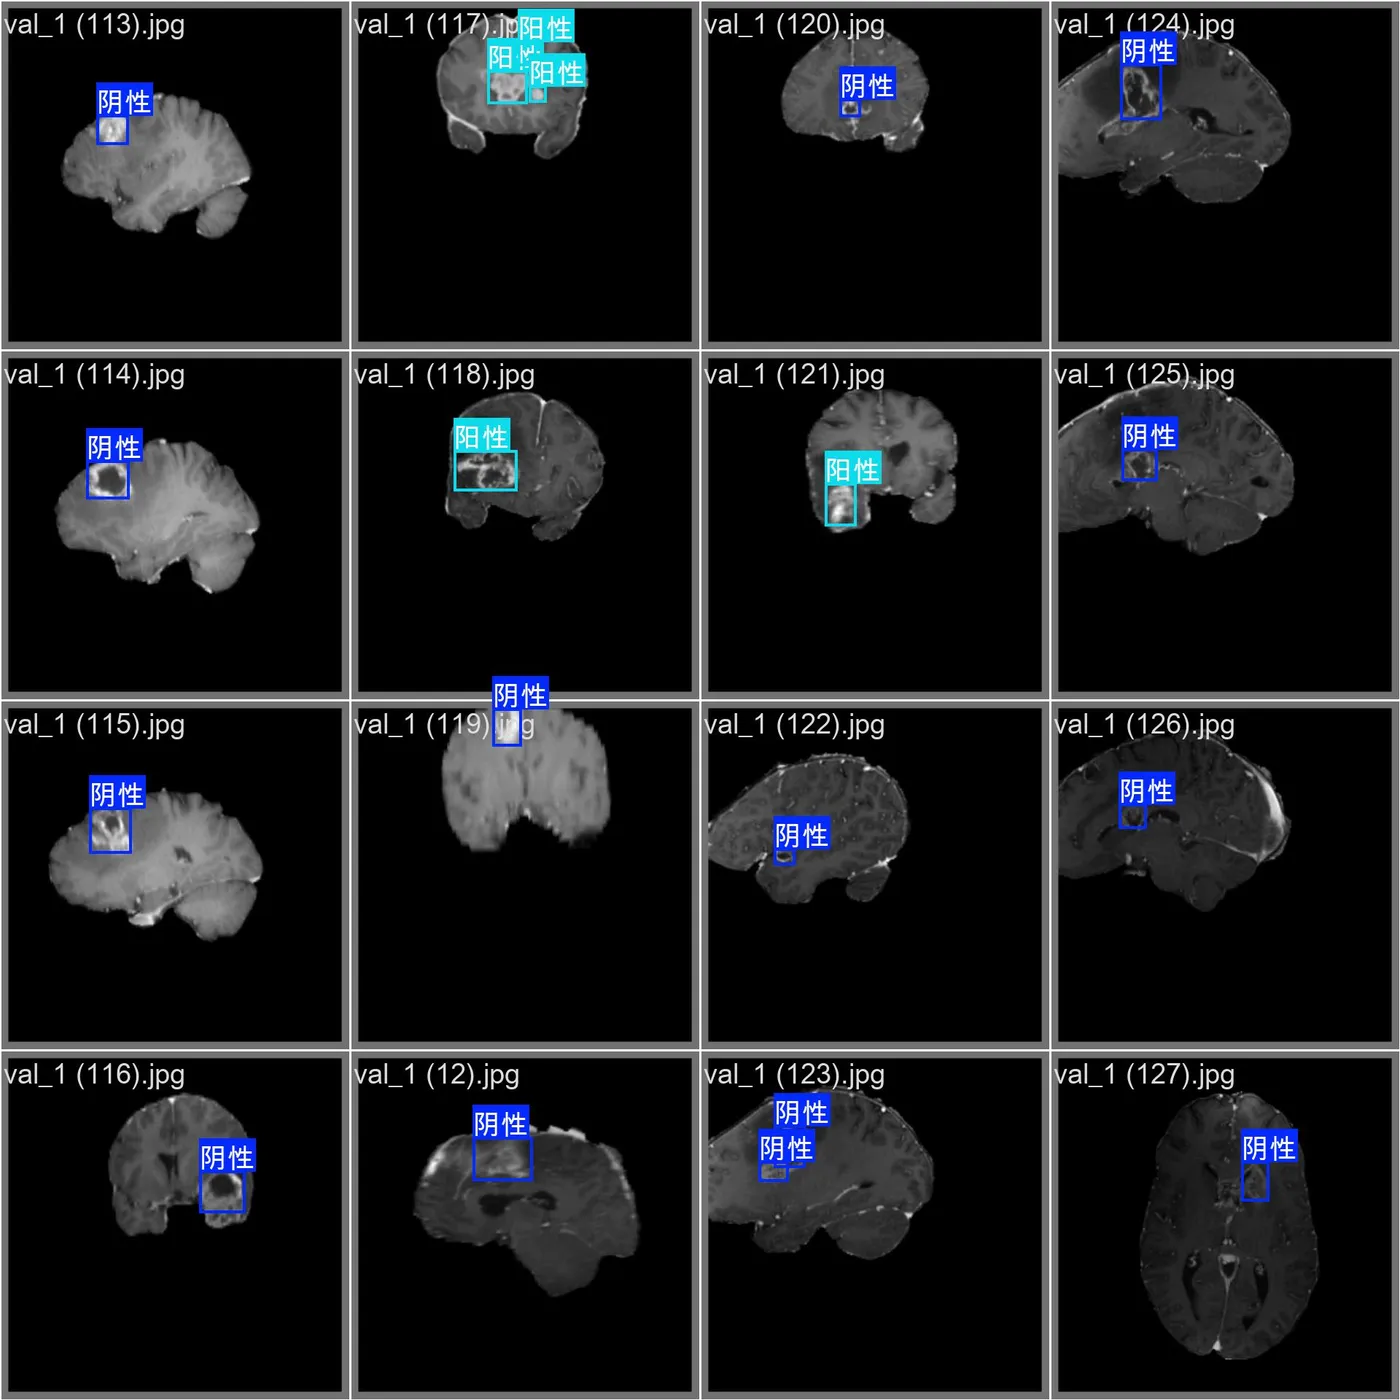

本数据集为脑肿瘤识别二分类数据集,共包含 1200 张高质量医学影像数据,面向基于深度学习的脑肿瘤辅助诊断任务构建。数据主要来源于脑部影像(如 MRI 等医学成像数据),经过严格筛选与人工标注,确保样本清晰、标签准确,适用于医学影像分类模型的训练与验证。

本数据集为二分类任务,共包含 2 个类别:

0: 阴性(Negative)—— 未检测到脑肿瘤

1: 阳性(Positive)—— 检测到脑肿瘤

数据覆盖不同成像角度、不同分辨率及不同肿瘤表现形式,能够帮助模型学习多样化的病灶特征,提高分类准确率与泛化能力。该数据集适用于 CNN、ResNet、EfficientNet、Vision Transformer 等主流图像分类网络结构的训练与实验对比,也可用于医学影像智能辅助诊断系统的算法验证。

本数据集共包含 2 个类别:

0: Negative

1: Positive

具体含义如下:

| 类别编号 | 类别名称 | 含义 |

|---|---|---|

| 0 | Negative | 未检测到脑肿瘤 |

| 1 | Positive | 检测到脑肿瘤 |

其中:

Negative 类别

表示影像中未发现脑肿瘤病灶,这类样本用于帮助模型学习正常脑组织特征。

Positive 类别

表示影像中存在脑肿瘤病灶,这类样本用于帮助模型学习肿瘤区域特征。

通过学习这两类样本,模型可以自动区分正常影像与病变影像。